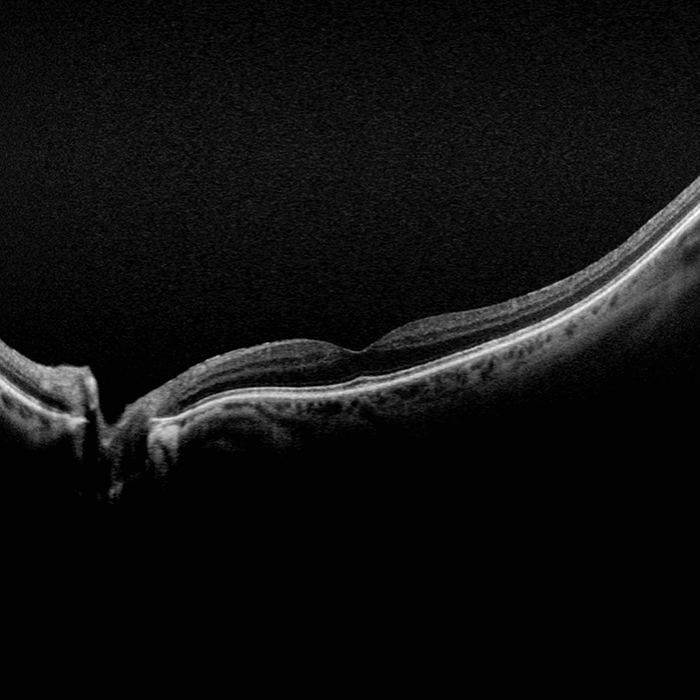

Silverstone, the most powerful tool yet for examining the retina, is the only ultra-widefield imaging device with integrated Swept Source OCT. Silverstone produces a 200° single shot retinal image of unrivaled clarity in less than ½ second and enables optomap guided SS-OCT scanning across the retina and into the far periphery.

optomap has been shown to enhance pathology detection and disease management and to improve clinic flow. Now with integrated Swept Source OCT, Silverstone facilitates examination of the retina from vitreous through the choroidal-scleral interface.

- OCT: Up to 23mm line scan and swept-source functionality